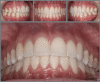

Introduction: The smile arc is an esthetic parameter that has been better investigated by Orthodontics after the "new esthetic paradigm". Its diagnostic evaluation and inclusion in the objectives of orthodontic planning has become fundamental for professionals seeking for more beautiful and youthful natural esthetic outcomes.

Objectives: To review concepts related to the smile arc, analyze the determinants of its appearance, understanding how the possible variations can affect the esthetic perception of smile.